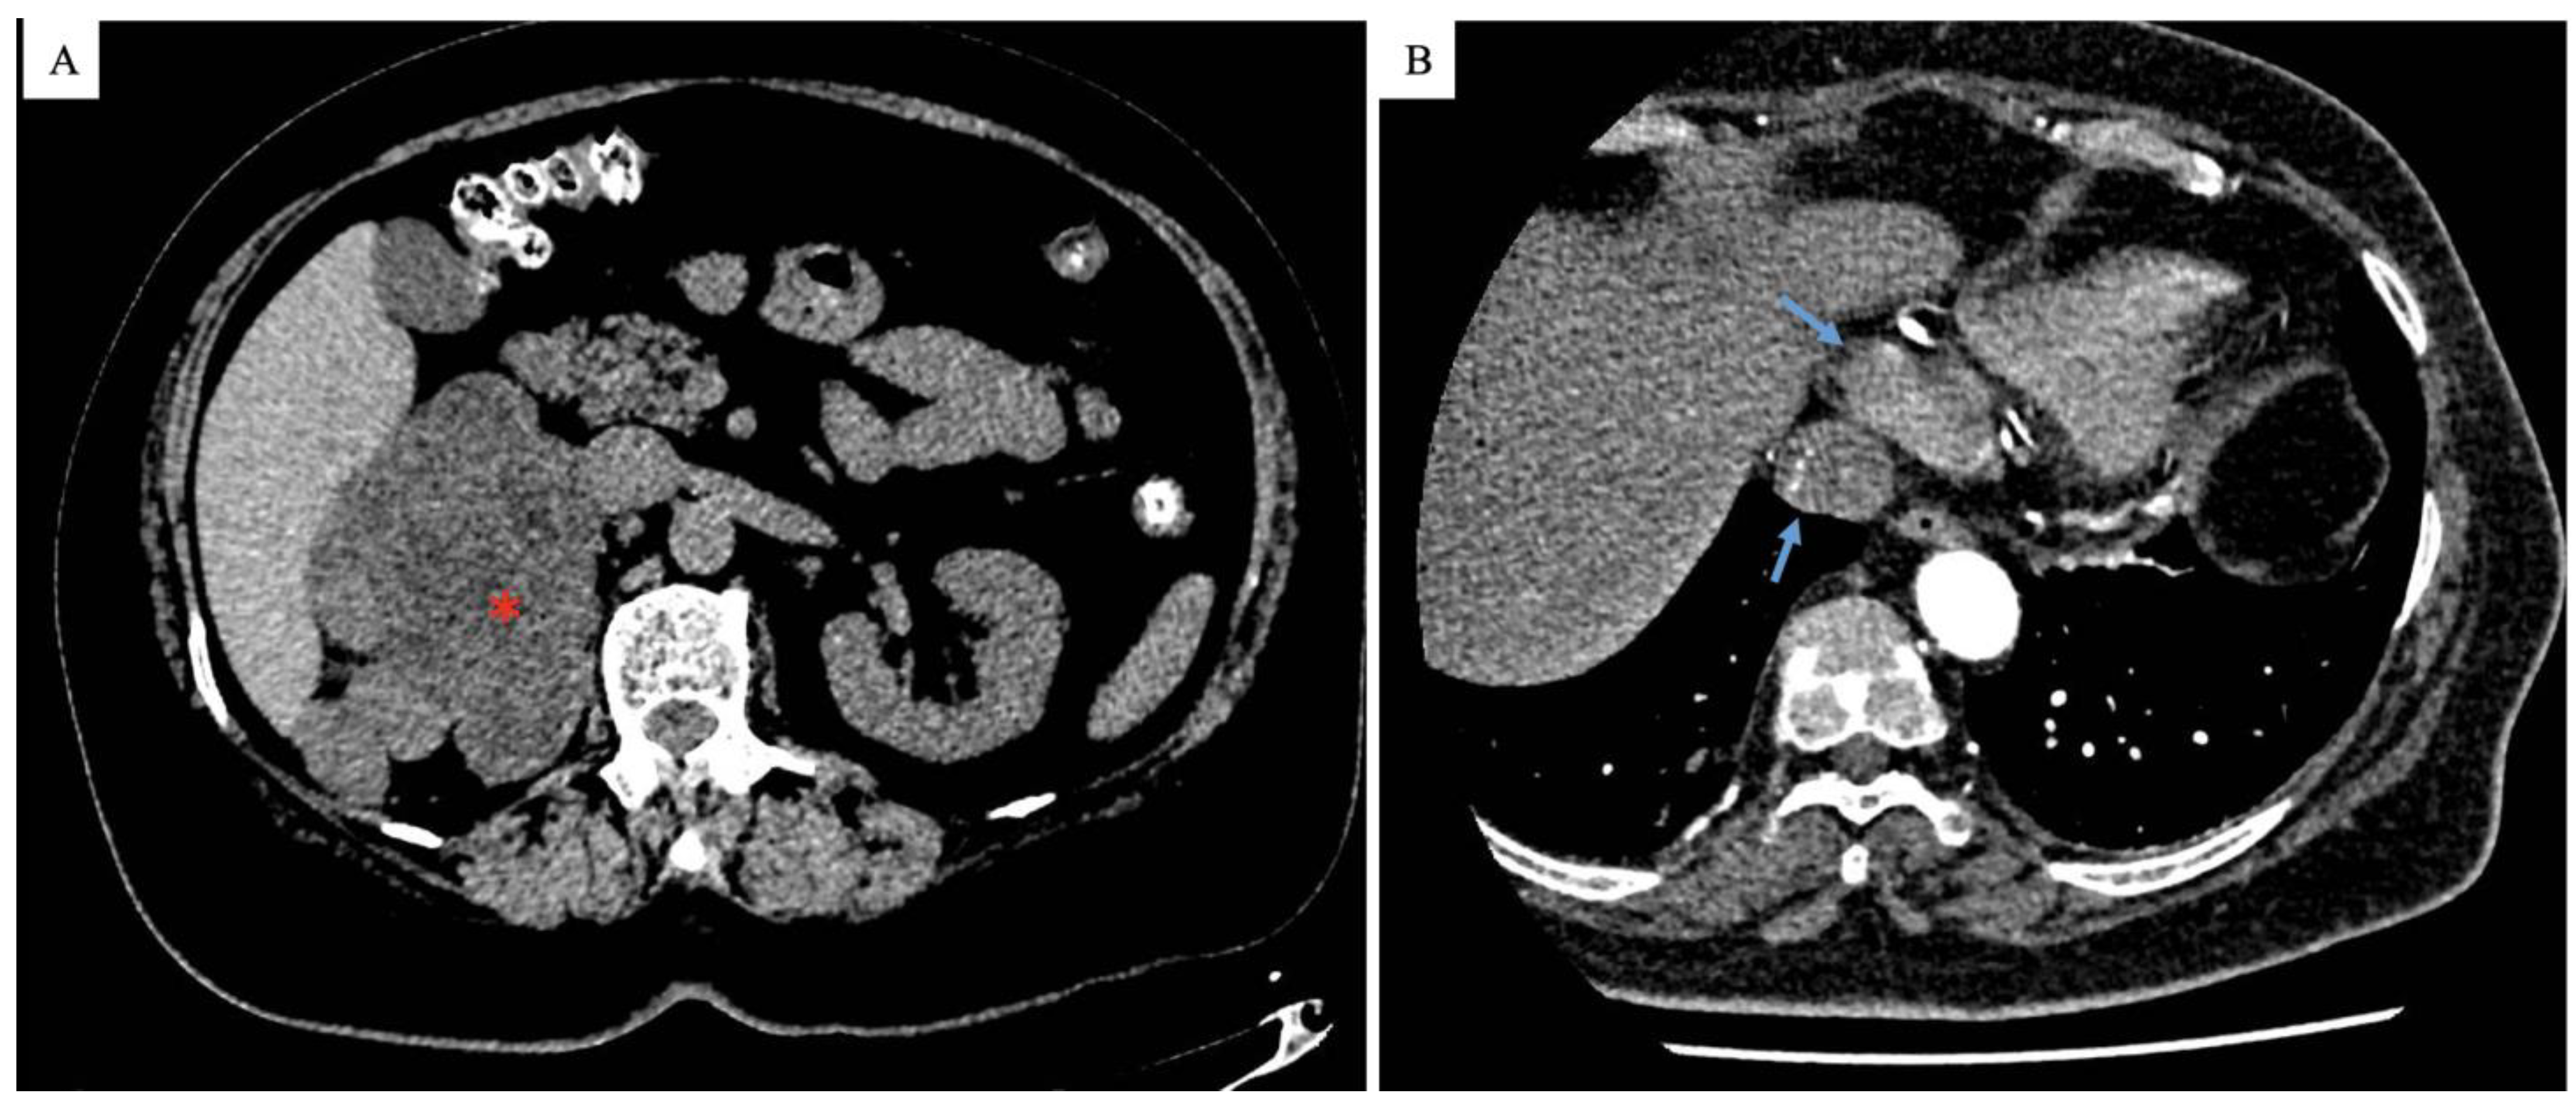

2. Case Presentation